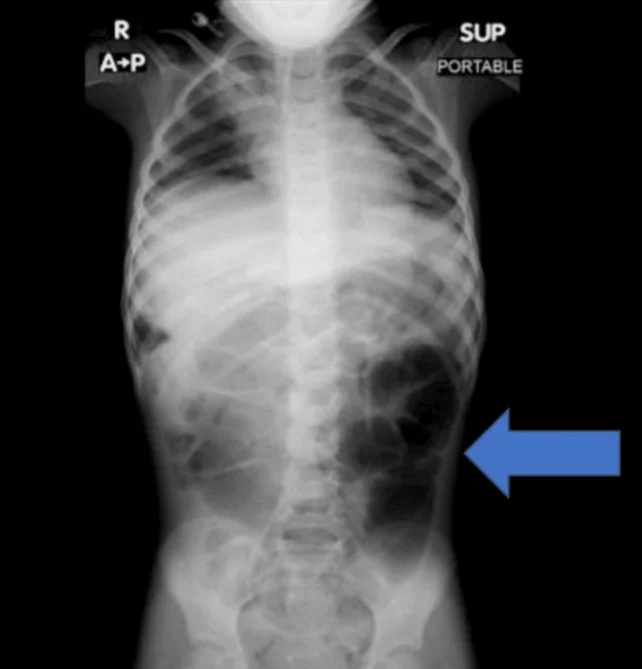

복통을 호소하던 6세 여아의 위장 안에서 예상치 못한 이물질이 발견된 사례가 학술지에 보고됐다. (사진=큐레우스 저널)

20일 의학 저널 '큐레우스(Cureus)' 실린 보고에 따르면, 사우디아라비아에 거주하는 6세 여자아이는 수주간 이어진 복통과 소화 장애 증상으로 병원을 찾았다. 정밀 검사를 진행한 결과, 의료진은 위 내부에 비정상적으로 큰 이물질이 자리 잡 것을 확인했다.

수술을 통해 제거된 물질의 정체는 다량의 머리카락이 엉켜 형성된 덩어리였다. 해당 덩어리는 위에 머무는 데 그치지 않고 소장 일부까지 길게 이어진 상태였던 것으로 전해졌다.

의료진은 보고서를 통해 "소아 환자에게 반복적인 복통이나 구토, 식욕 저하 증상이 장기간 지속될 경우 위장관 내 이물질 가능성을 염두에 둬야 한다"며 "영상 검사를 통한 조기 진단과 신속한 치료가 중요하다"고 강조했다.